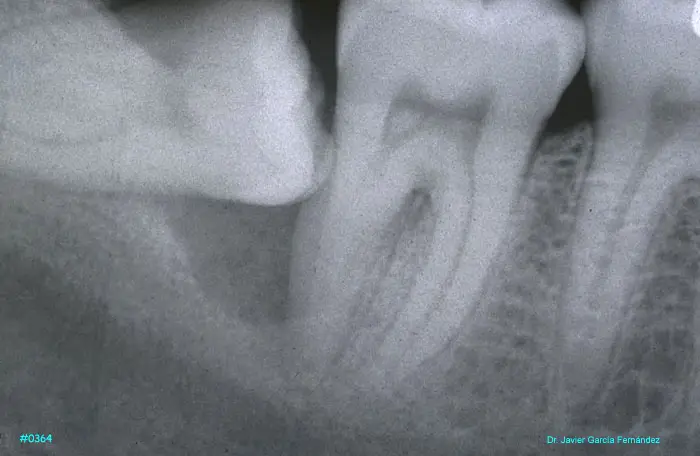

ATLAS DE CIRUGIA PERIODONTAL

image414